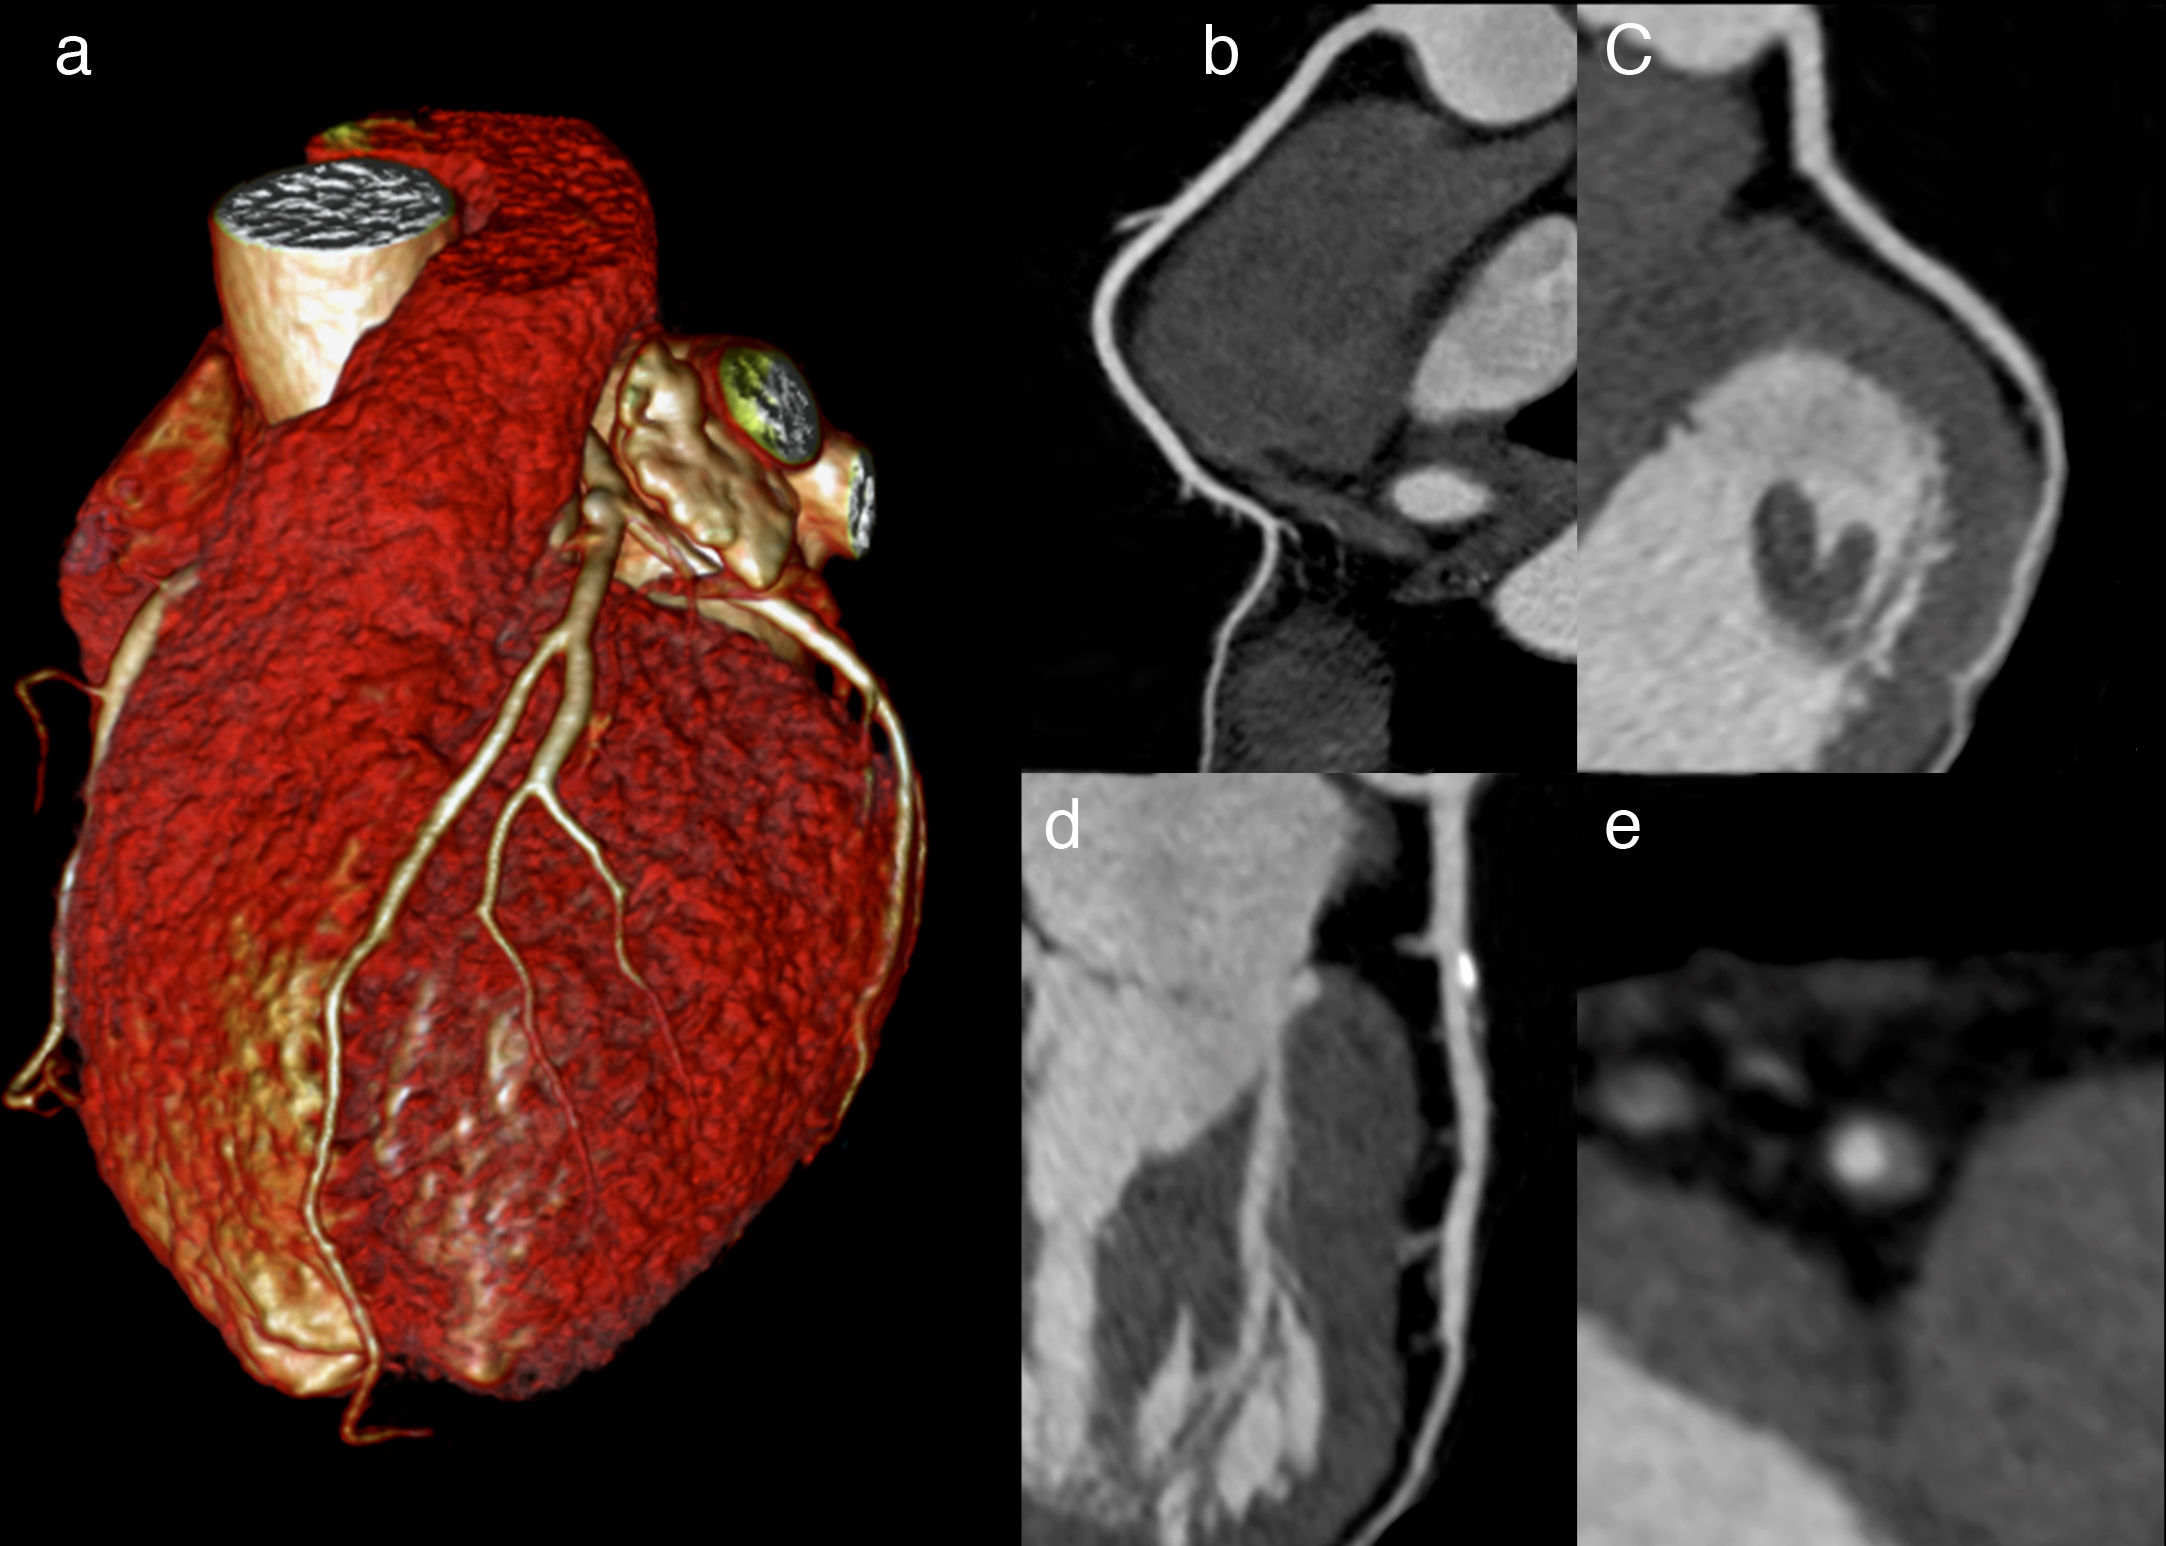

Coronariografía por tomografía computada vs Prueba de esfuerzo en el diagnóstico de enfermedad coronaria

Ambas estrategias tuvieron similar mortalidad y necesidad de internaciones, si bien la tomografía computada mostró reducción de infartos de miocardio y aumento de procedimientos invasivos diagnósticos y terapéuticos. JAMA Internal Medicine, 2 de octubre de 2017